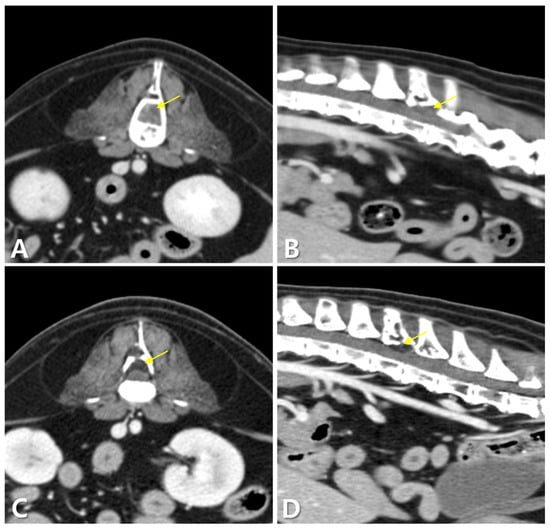

2. Case Description